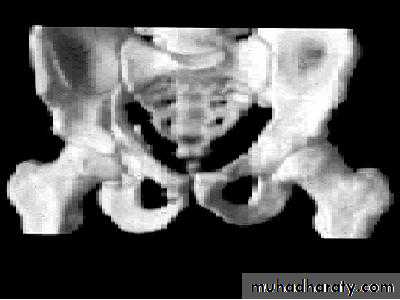

INTRA CAPSULAR FRACTUREfracture neck femur

Pathological anatomy and classification

The most useful is that of garden which is based on amount of displacement apparent in the pre-reduction x-ray of the neck femur.